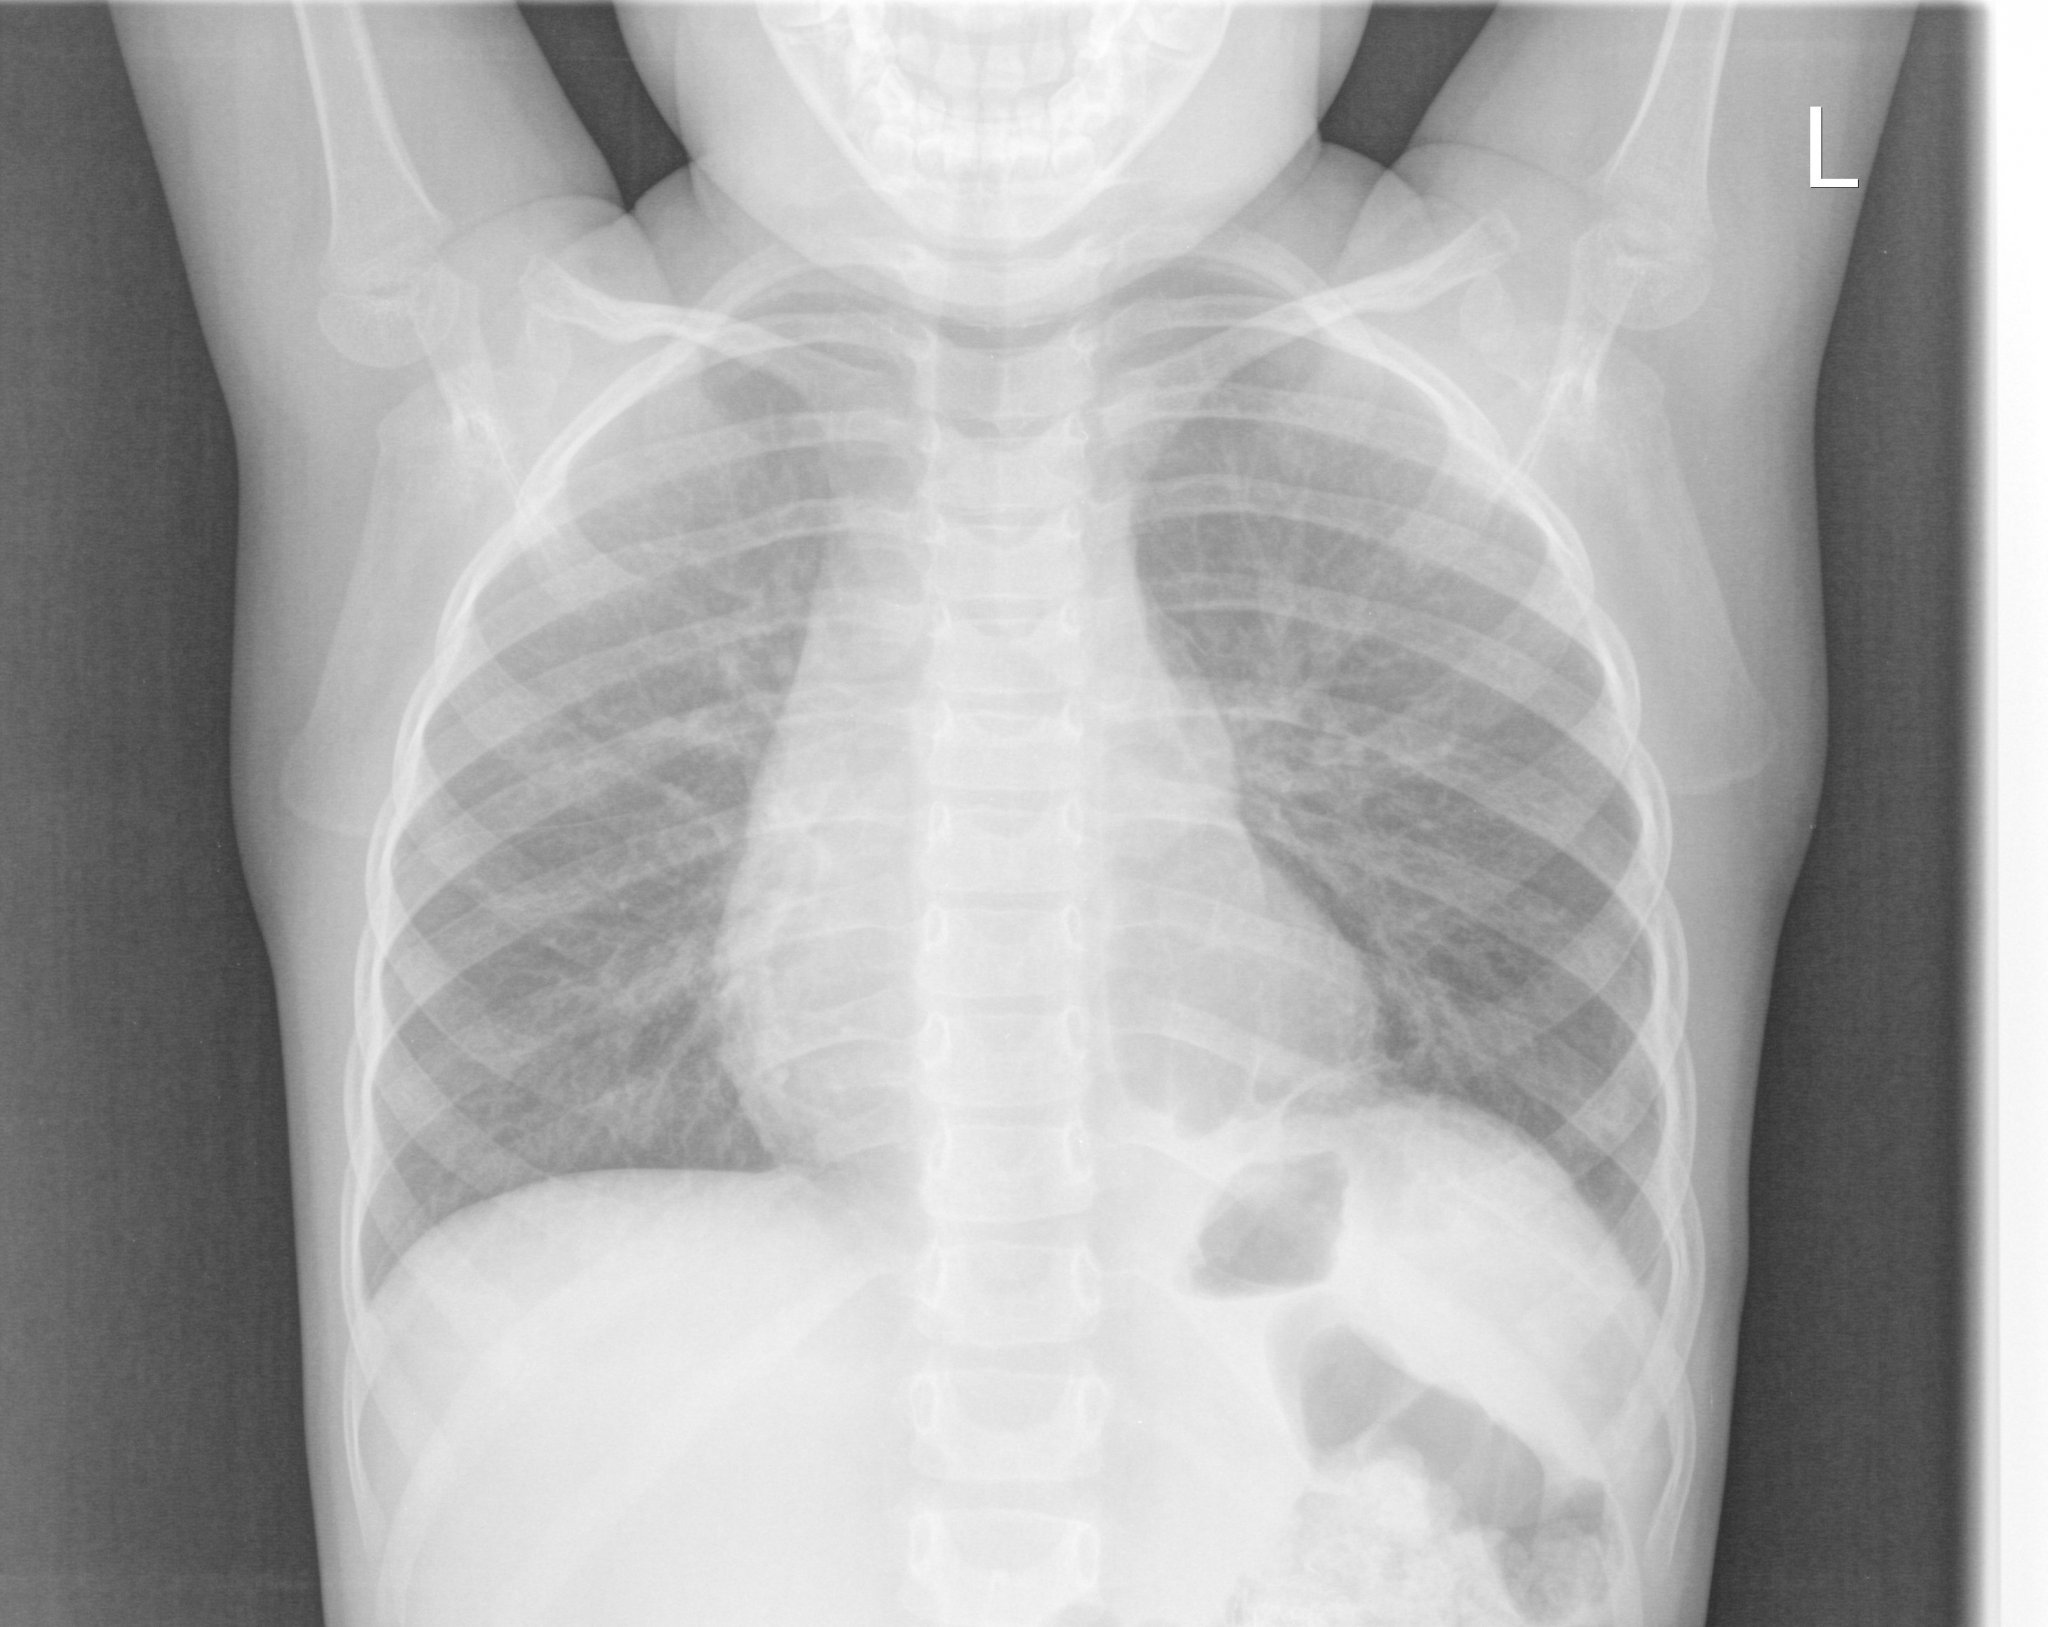

Д-р Огнян Брайков е детски хирург с богат опит в областта. През последните 4 години той оперира деца в хирургията на болница "Токуда" в София. Специализира в хирургични проблеми на ингвиналната област, кожни тумори, хемангиоми, пъпни хернии, кистични съдови аномалии, както и операции на хранопровода и коремната кухина.